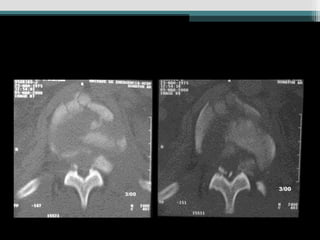

Caso 3 (24 anos, queda Fk e)

Caso 4 (19 anos, auto, Fk e)

Caso 3 (24anos, queda Fk e)

Caso 4 (19anos, auto, Fk e)